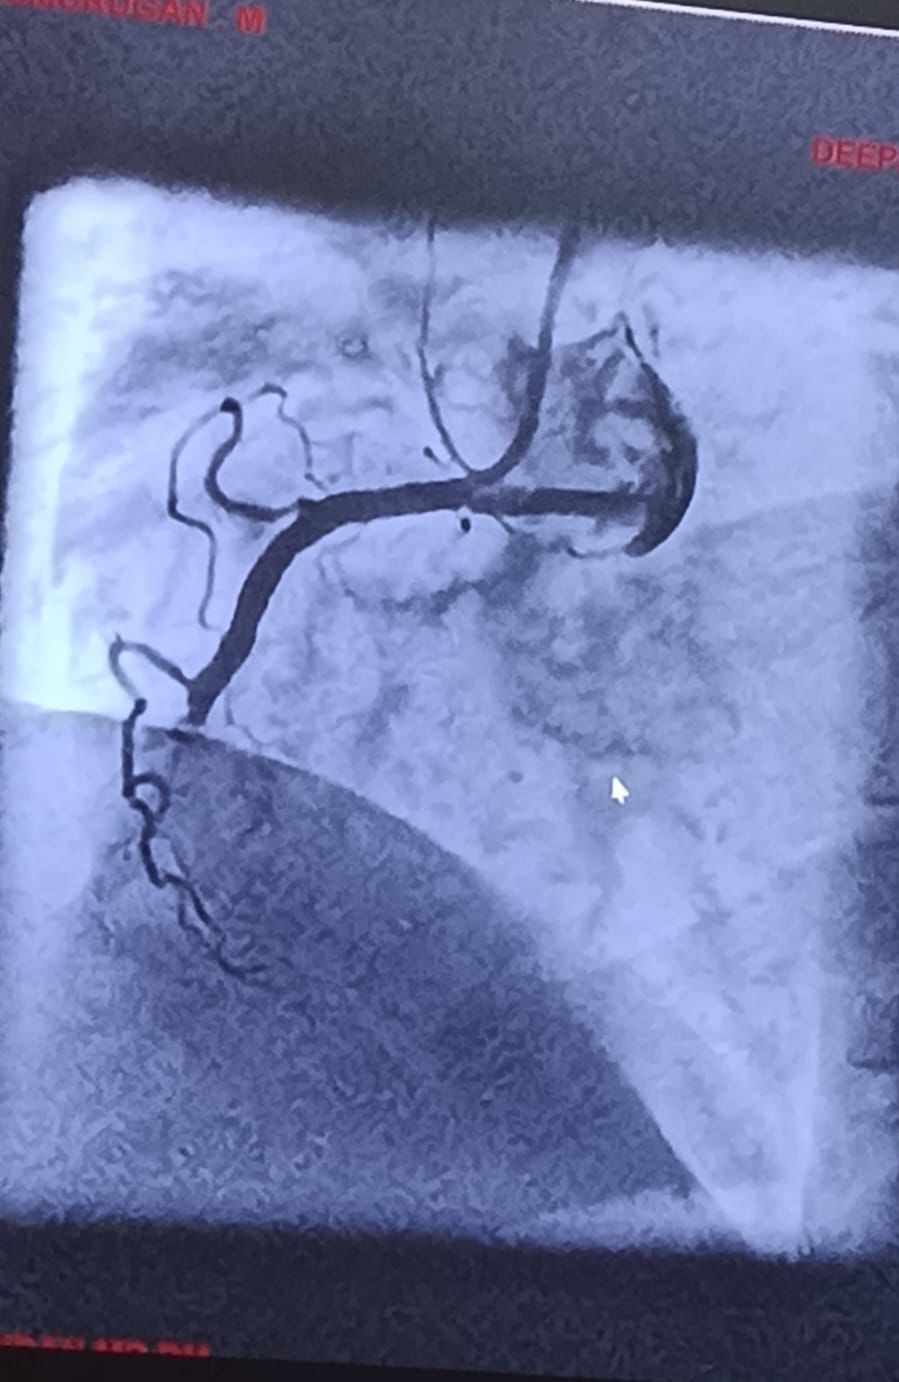

Deepa Kannan Hospital Heart Care Center & Cath Lab stands as a beacon of excellence in cardiovascular medicine. With state-of-the-art catheterization laboratory facilities and a team of renowned cardiac specialists, we are committed to providing comprehensive heart care services that combine cutting-edge technology with personalized patient care.

State-of-the-art cardiac catheterization laboratory with advanced imaging technology